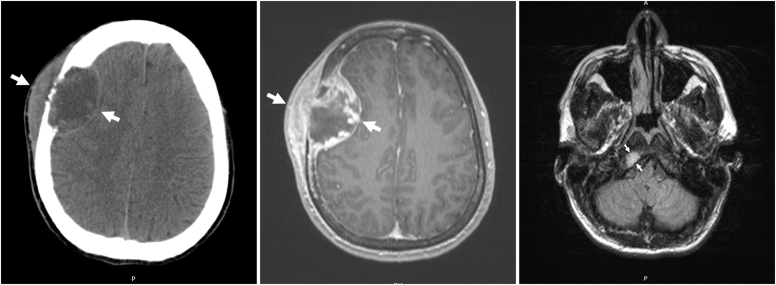

Our patient was a 31-year-old man diagnosed with periaortic PGL and succinate dehydrogenase subunit B pathogenic variant at the age of 9 years with cardiac arrest. He developed intra-abdominal and skeletal metastatic disease by the age of 14 years and treated with surgery, chemotherapy, and radiation. After being lost to follow-up, the patient presented emergently with headache, palpitations, hypertensive crisis, type 2 non-ST-elevation myocardial infarction, and catecholamine-induced cardiomyopathy, with plasma free metanephrine level of 61.0 pg/mL (0.0-88.0 pg/mL) and elevated serum free normetanephrine level of 662.9 pg/mL (0.0-210.1 pg/mL). Imaging showed a right frontal calvarial lesion, with 4.9-cm intracranial dural and 4.9-cm extracranial components, and a 1.5-cm occipital bone lesion. Following adrenergic blockade, the patient underwent resection of the frontal lesion with pathology showing metastatic PGL.